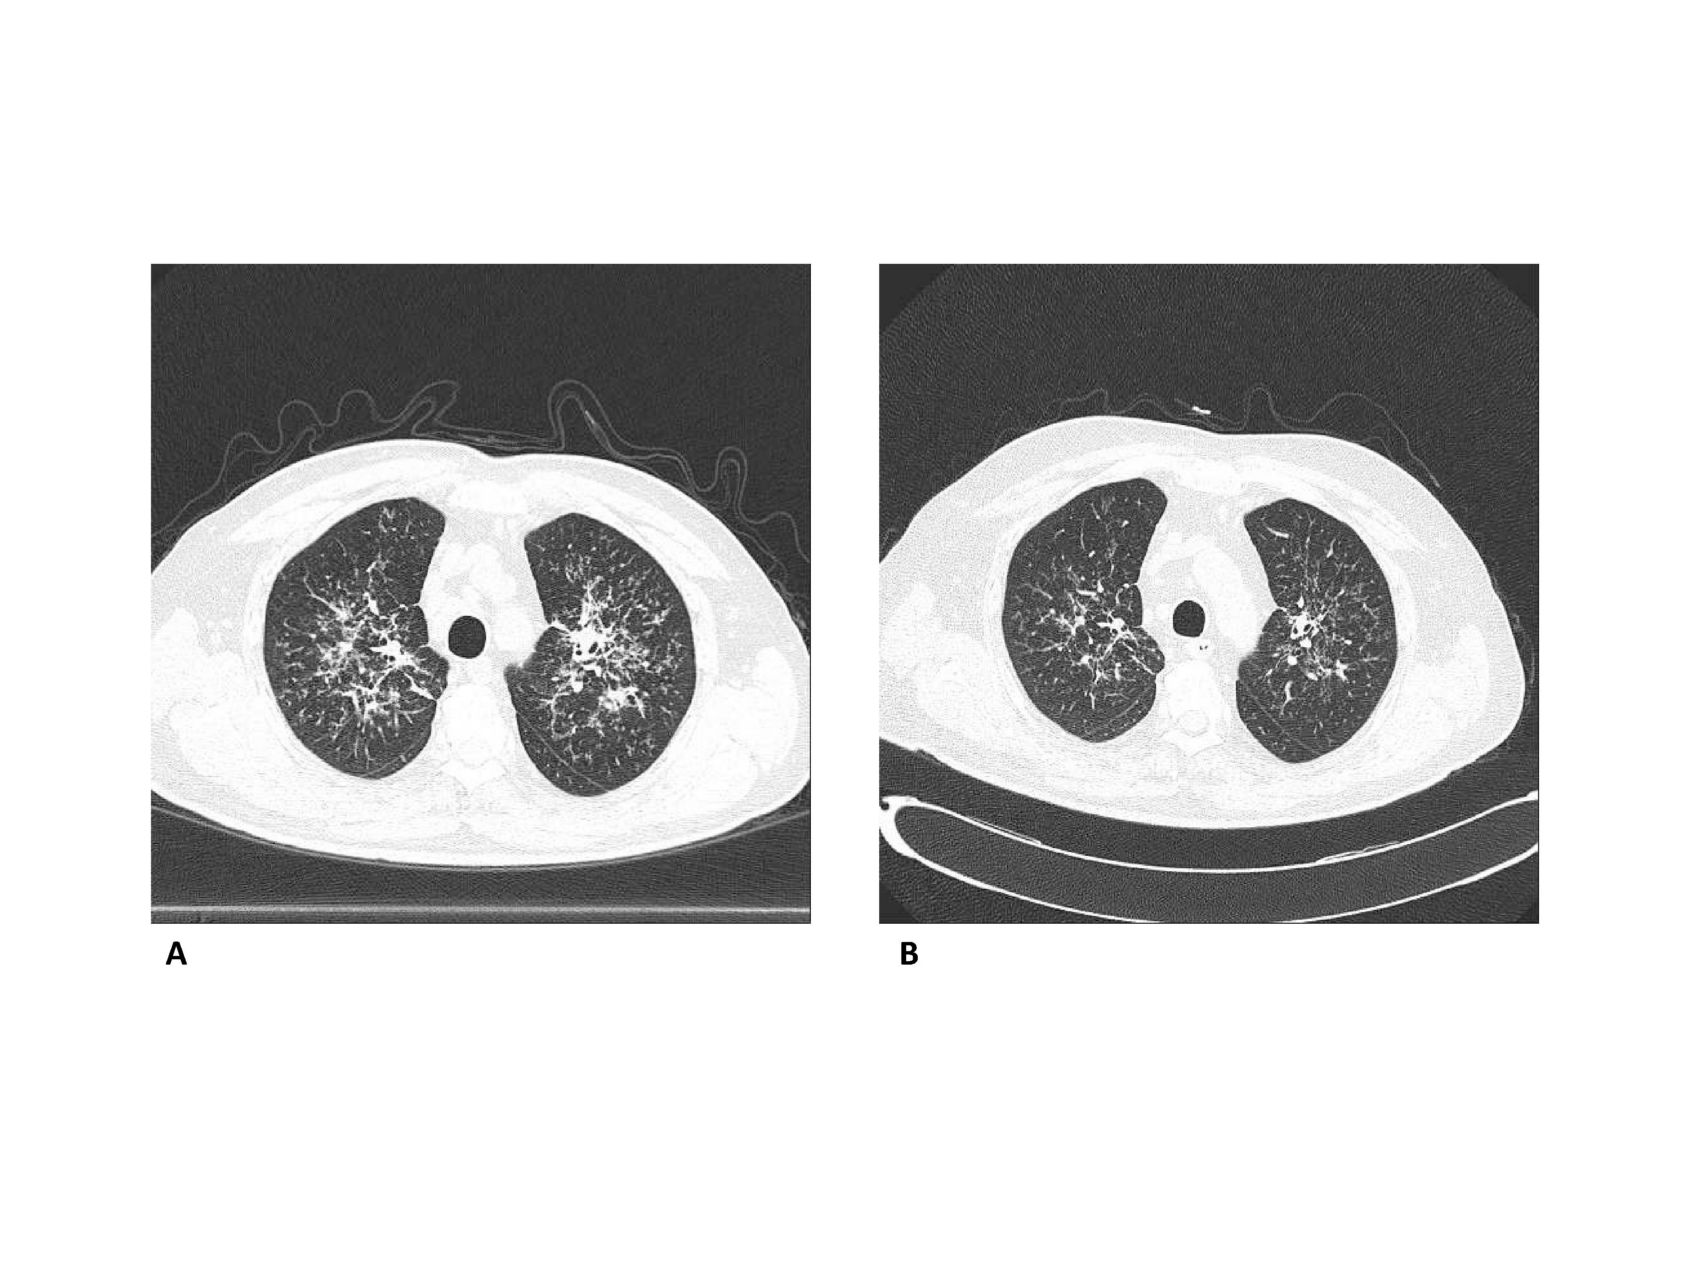

588_Immaginisarcoidosi[2]